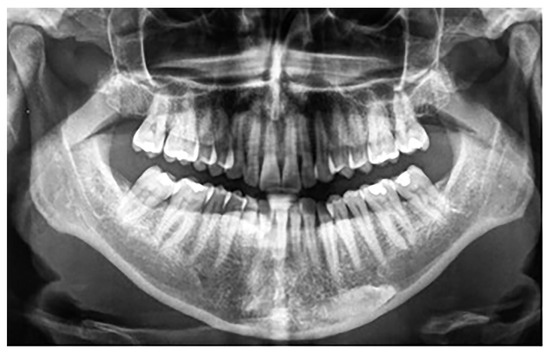

Besides these 25 patients with mandibular canine impaction, 4 of 1479 participants, three females and one male, were found to have mandibular canine transmigration. Considering the small size of the sample, no gender differences were observed. All patients had retained primary canines. In all four cases, the transmigrated canines were unilateral and impacted, with three involving the right side and one on the left side. Two canines were associated with dentigerous cysts. Of the four transmigrated mandibular canines in the present study, one was classified as type 1 and three were classified as type 4 according to Mupparapu’s classification (Figure 3). The summary of these findings is shown in Table 3.

Figure 3.

Patient with a Type 4 transmigrated right mandibular canine.